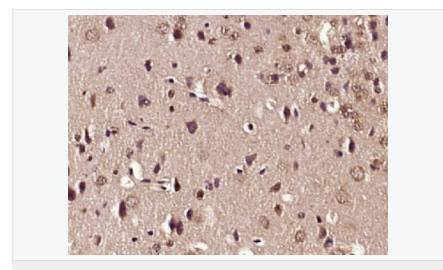

交叉反應(yīng):Rat,Mouse,Human(predicted:Sheep,Rabbit,Horse,Cow,Pig,Dog) 推薦應(yīng)用:IHC-P,IHC-F,IF,ELISA

| 產(chǎn)品應(yīng)用 | WB=1:500-2000 ELISA=1:5000-10000 IHC-P=1:100-500 IHC-F=1:100-500 ICC=1:100-500 IF=1:100-500 (石蠟切片需做抗原修復(fù)) not yet tested in other applications. optimal dilutions/concentrations should be determined by the end user. |